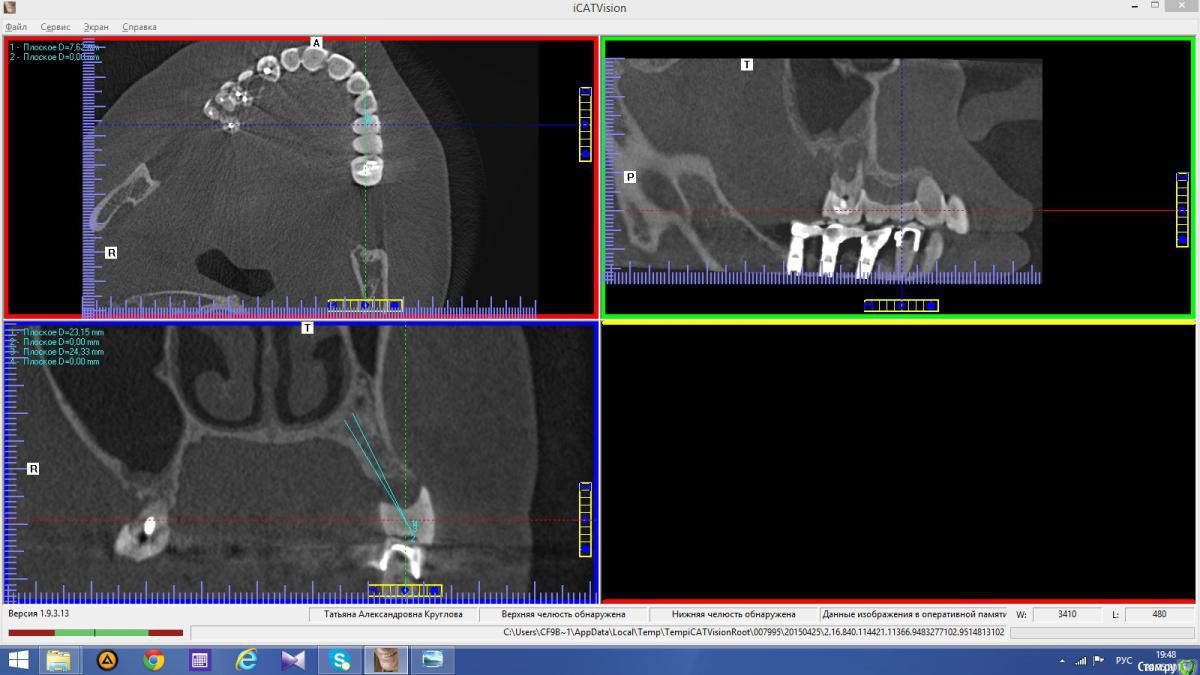

Популярный пост Abuk Опубликовано 24 ноября, 2015 Популярный пост Поделиться Опубликовано 24 ноября, 2015 Планировали 8 имплантатов.Буду рад конструктивной критике.Фото с мокап.Через 6 днейДалее хотели поставить 6 ки, она отказалась (не хотели синусы)и решили все по-другому .Через 2мес пришла с отколотыми консолями )Прошу прощения ,что ортопедию выложил не в том разделе), не хотел делить. 26 1 Ссылка на комментарий

Abuk Опубликовано 24 ноября, 2015 Автор Поделиться Опубликовано 24 ноября, 2015 Снимки не могли бы показать? .все что есть готовое. Ссылка на комментарий

Abuk Опубликовано 24 ноября, 2015 Автор Поделиться Опубликовано 24 ноября, 2015 (изменено) Радикально Вы. Что оставили ей после имплантации-это инд аббатменты? На них мокап одели и нагрузили сразу? У всех был торк хороший? Или это временные абб? Что за систему использовали? В планах консоль назад, правильно я понимаю?Спасибо.увидев такую работу,сам так же подумал бы). Но там подвижность 2-3 ст. ближе к 3. Мосты болтались ,2 ки в хлам. 1 ки только стабильны. Снимал мосты,проводил кюретаж. Решил дернуть.Абатманы временные, тех. сделал на них коронки. Система анкилоз. Работа,на посл. фото, постоянная . Имплы в области 4 и по одному моляру ,консоли. Мок ап был до имплантации . По нему шаблон. Стабильность 15 -20 на 23 , остальное больше 30. Изменено 24 ноября, 2015 пользователем Abuk 1 Ссылка на комментарий